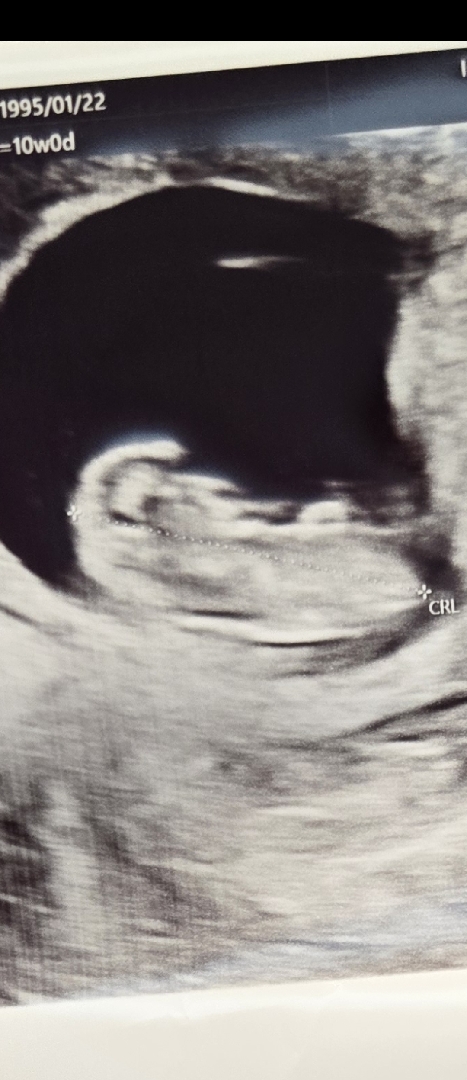

초음파를잘못찍어주신거겠죵 ㅠㅠ 10주0일차 우리칠폭이 초음파에용 ㅎㅎ 위치가이상해서그런가 둥글둥글하지않고 특이하네요🤣 3.4cm

손을머리에올리고있는건가 ㅎㅎ